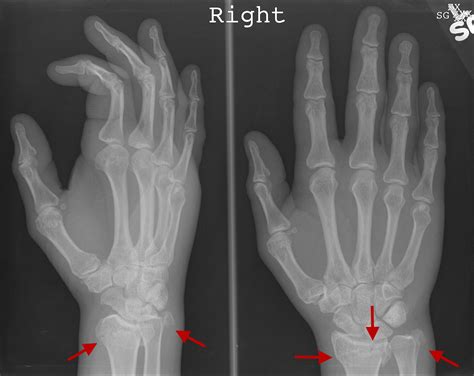

Diagnosing an Ulnar Styloid Fracture

Diagnosing an ulnar styloid fracture typically involves a combination of physical examination and imaging tests. The diagnostic process may include:

• Physical Examination: A healthcare provider will assess the wrist for pain, swelling, and deformity. They may also check the range of motion and stability of the wrist.

• X-rays: These are the primary imaging tool used to confirm the diagnosis. X-rays can show the location and extent of the fracture.